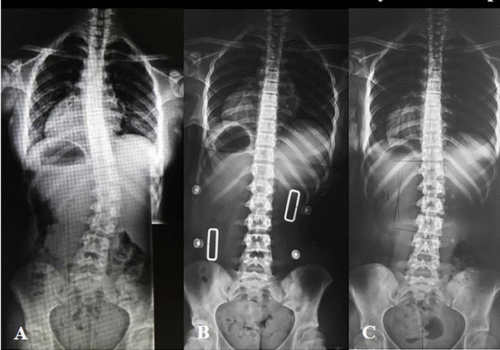

الكشف المبكر: كلما اكتُشف الجنف في مراحله الأولى، زادت فرص العلاج بدون جراحة.

الأحزمة الطبية المتقدمة PioBrace: تساعد في تثبيت العمود الفقري ومنع التفاقم أثناء النمو.

المتابعة المنتظمة بالأشعة: لمراقبة زاوية كوب بشكل دوري.